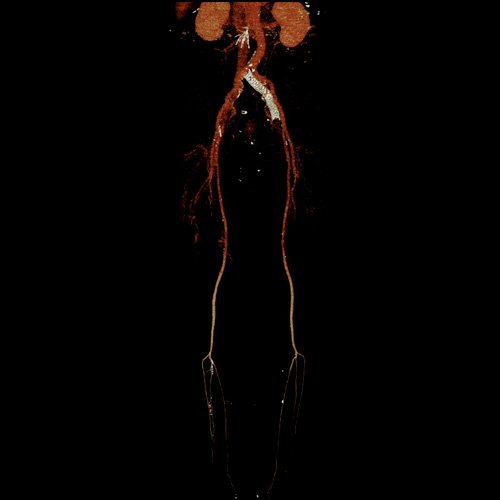

• AngioTAC de miembros inferiores (Día 0): Ateromatosis parietal calcificada parcheada en todo el territorio aorto-ilíaco-femoral bilateral. LADO DERECHO: Arteria ilíaca interna: de calibre y trayecto conservado, permeable. Arterias ilíaca externa y femoral común: de calibre y trayecto conservados, permeables. Arterias circunfleja ilíaca superficial y epigástrica superficial: de calibre y trayecto conservados, permeables. Arteria femoral superficial: de calibre y trayecto conservado, permeable. Arteria femoral profunda: de calibre y trayecto conservado, permeable. Arterias circunflejas femoral medial y lateral: de calibre y trayecto conservados, permeables. Arteria poplítea: de calibre y trayecto conservado, permeable. Arteria tibial anterior: de calibre y trayecto conservado, permeable. Arteria tibial posterior: de calibre y trayecto conservado, permeable. Cambios artrodegenerativos coxo-femorales y tricompartimentales en la rodilla. Signos de entesopatía cuadricipital distal. No se observan alteraciones a nivel de los grupos musculares visualizados. La disposición del tejido graso es normal. LADO IZQUIERDO: En fase angiográfica se observa menor calibre y opacificación de las arterias femoral superficial y profunda, poplítea y de sus ramas musculares en muslo y pierna en comparación con el miembro contralateral, con opacificación arterial preservada. En fase venosa se evidencia mayor la densidad endovascular de las mismas hasta el tercio distal de la pierna, donde se logran identificar a las arterias peronea, tibial anterior y tibial posterior. Se evidencia un defecto de relleno de la vena ilíaca común izquierda, en su nacimiento, en relación a trombosis venosa profunda. No se identifica compromiso de la porción visualizada de la vena cava inferior ni del sistema venoso ilíaco contralateral. Se visualiza aumento del tamaño de todos los grupos musculares del muslo izquierdo con respecto al contralateral y retardo de la concentración de contraste, asociado a edema de los tejidos blandos superficiales. Reticulación de la grasa de la región inguinal. Cambios artrodegenerativos coxo-femorales y tricompartimentales en la rodilla. Signos de entesopatía cuadricipital distal. No se observan alteraciones a nivel del fémur ni de las porciones visualizadas de la tibia y el peroné.

Angio TAC de miembros inferiores (Día 0)